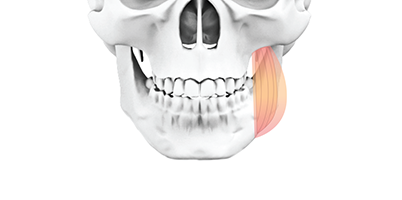

근육절제술

저작근육 교근 안쪽부분을 절제하여 근육의 전체적인 두께를 줄여주고, 피질골 절제술과 병행하여 정면 효과를 높입니다